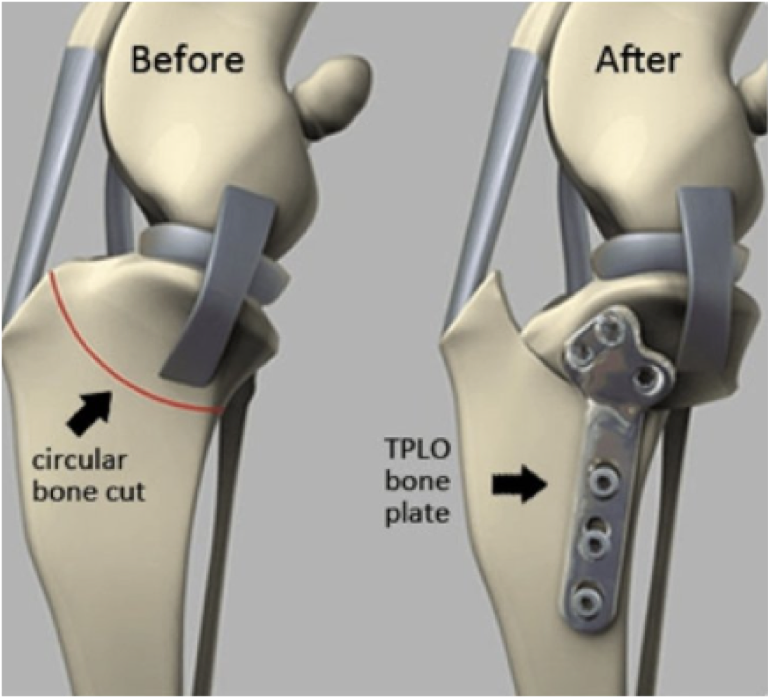

Tibial Plateau Leveling Osteotomy (TPLO)

When a dog bears weight on a damaged or torn ACL, the femur tends to slide down the back slope of the tibia, causing instability and discomfort. The TPLO procedure addresses this by altering the tibial plateau angle, stabilizing the joint and potentially preserving any remaining healthy ACL fibers. This involves performing an osteotomy (bone cut) to rotate the tibial plateau into a more stable position. Over the last 30 years, TPLO has become the gold standard in specialty ACL surgery for dogs, boasting a high success rate of 90-95% and reliably restoring knee stability and mobility. We have had good success with this technique at Santa Ynez Pet Hospital.

- An Improved Osteotomy: Both TPLO and CBLO elegantly employ a crescentic saw blade to create a curved osteotomy with which bone fragments can be rotated into position. The CBLO uses a dome-shaped or convex crescentic osteotomy through the shaft of the tibia and does not affect the joint nor damage growth plates in young animals. Conversely, the TPLO involves creating a scoop-shaped crescentic osteotomy which starts inside the knee joint and exits through the back of the tibia. This increases the risk of bacterial contamination through the osteotomy (you can never truly close the joint), and carries a risk of leaving a thin stalk of bone at the front of the tibia which can – on rare occasions – fracture despite taking precautions.